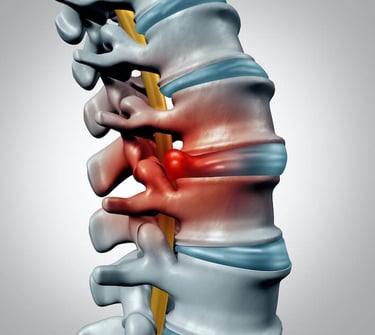

¿Qué es un Disco Herniado?

Un disco herniado ocurre cuando uno de los discos intervertebrales de tu columna se desplaza de su lugar o se rompe, presionando los nervios cercanos. Esto puede provocar dolor intenso, adormecimiento o hormigueo, especialmente en la espalda, cuello, brazos o piernas. Ya sea causado por una lesión, mala postura o el desgaste natural del envejecimiento, este problema común puede afectar significativamente tu calidad de vida.